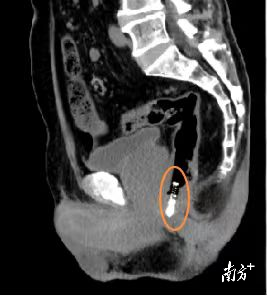

急诊医生了解情况后,为孔大爷安排全腹CT检查,发现直肠-肛内异物存留,立即请普通外科医生急会诊。普通外科医生周昆仔细询问患者病史、认真查体,在急诊科医护团队协作下,为孔大爷取胸膝位,为其行肛门指诊,发现进指约3cm处可触及笔尖,请示上级医生后,决定为孔大爷行肛门镜下直肠内异物取出术。很快,医生用一把弯钳完整取出异物,长约10cm、直径1cm的塑料材质圆珠笔。